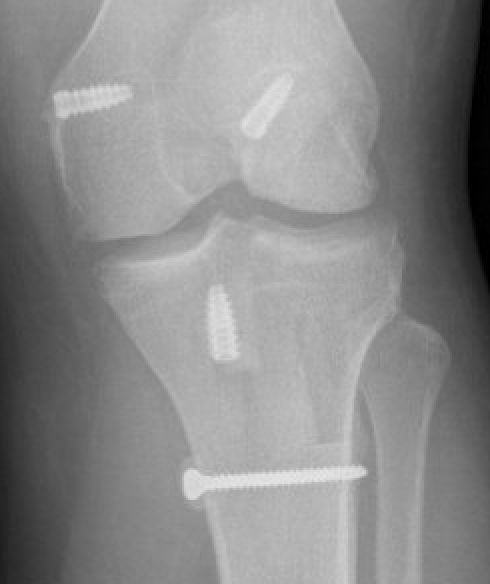

MCLRMCLRMCLR

MCLRMCLR